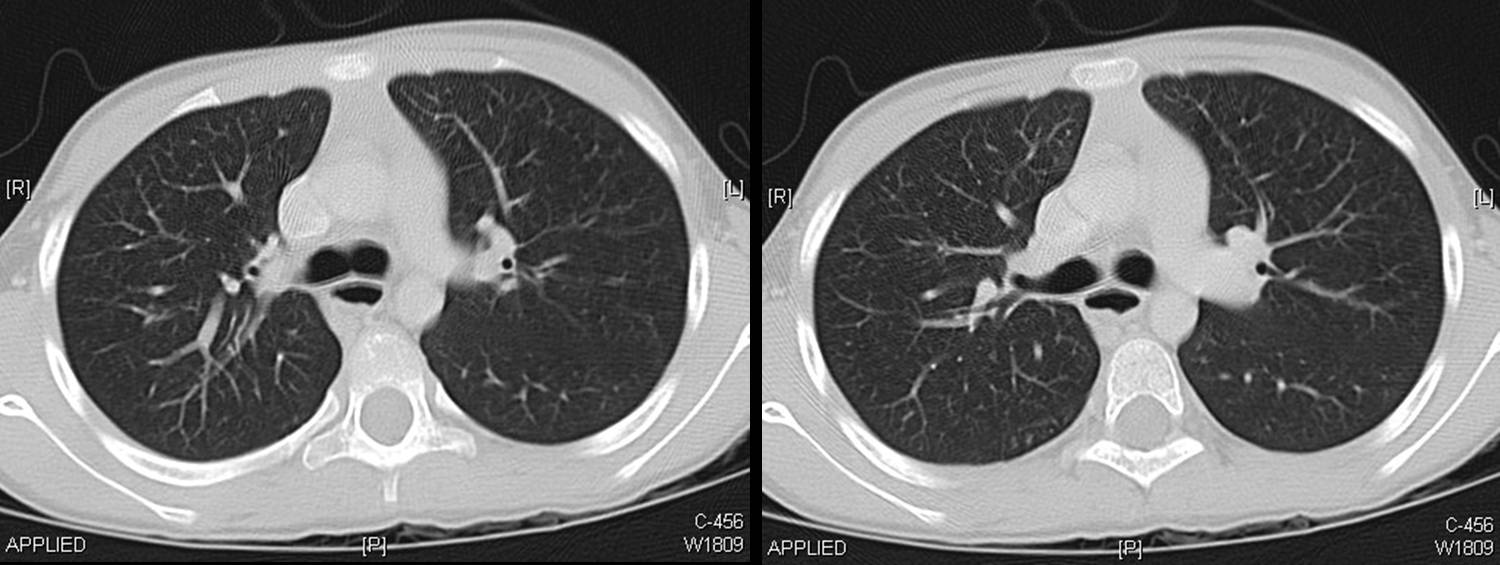

A CT scan of chest was done.

The following screen shows the images from the Chest CT.

| Figure 4-a | Figure 4-b | Figure 4-c |

| Figure 4-d | Figure 4-e | Figure 4-f |

| Figure 4-g |